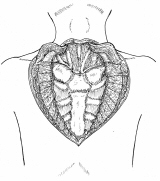

前頚部展開法最新モデル2006

胸襟を開き合える仲間は貴重ですね。